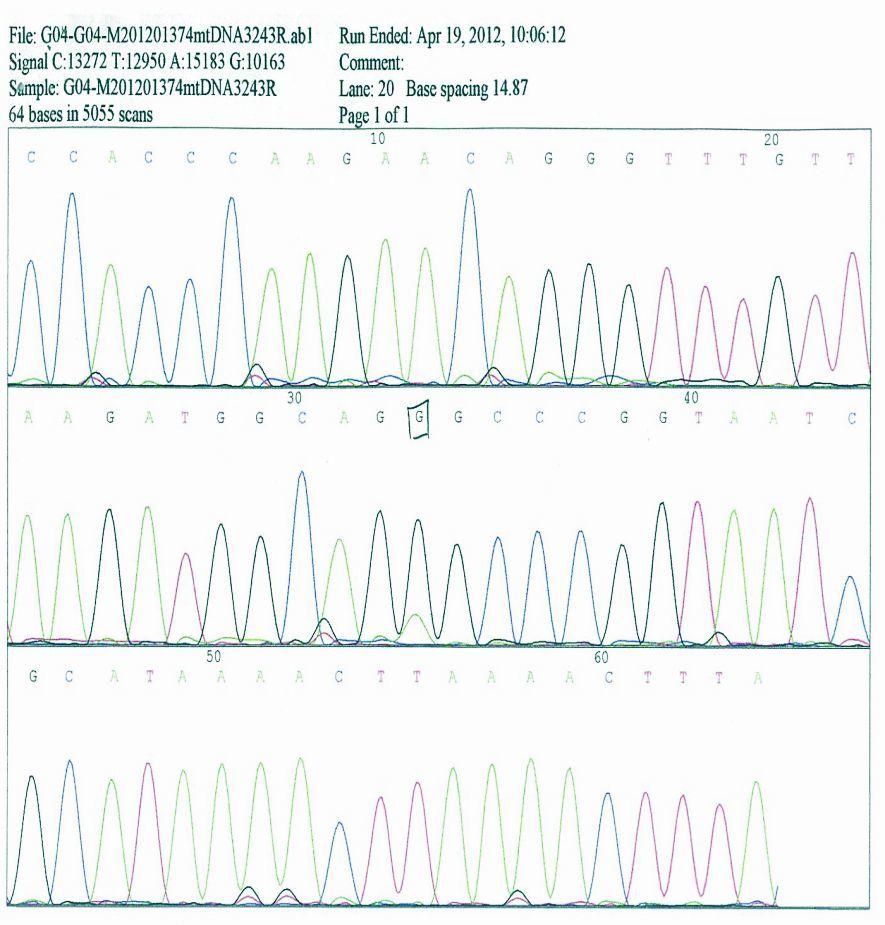

患者杨某,男性,49岁,其母亲有糖尿病病史。于2011年8月15日无明显诱因下出现头痛,以前额为明显,无恶心、呕吐,无双侧眼球一过性黑朦,无二便失禁。当时症状可耐受,未引起注意,同年8月17日家人发现患者反应迟钝、行为异常,言语不能伴有意识模糊,8月18日晨急诊来本院就诊,体温37.6℃,入院途中呕吐一次,非喷射性。急诊行头颅CT检查:左侧额叶稍低密度影。门诊拟“中枢神经系统感染待排”收入院进一步检查、治疗。入院后急诊头颅MRI检查:左侧额叶及皮层下可见片状长T1、T2信号影,轻度脑萎缩,伴脑室扩大,考虑缺血性病变。行脑电图检查:广泛、弥漫性异常改变,可见棘慢波综合、尖慢波综合。心电图为ST-T改变。18日上午10点左右突发意识丧失,面色发绀,牙关紧闭,口吐白沫,口中异常尖叫声,双眼上翻,四肢呈强直性抽搐,头后仰,小便失禁,给予静脉推注地西泮后,症状持续2 min左右抽搐停止,约10 min后神志恢复,对发生事件无记忆。查体:颈软,未见其他阳性神经系统定位体征。给予甘露醇脱水降低颅内压治疗,给予供氧,维持水电解质平衡治疗,考虑中枢神经系统感染引起继发性癫痫发作可能,给予更昔洛韦静脉点滴抗病毒。脑脊液:正常。因患者反复抽搐伴发热,家人要求去外院进一步治疗。外院住院期间诊断糖尿病,经治疗后症状稳定,出院。2012年春节再次抽搐,表现为发热,抽搐,智力明显下降,听觉减退,反应迟钝,消瘦,活动后乏力。相关检查提示线粒体脑病。诱发定位检查:听觉诱发定位(ARB)左侧80 db声强刺激仅引出V波,100 db刺激引出各波各峰间期正常;视觉诱发电位:双侧p1波潜伏期延长;正中神经体感诱发电位(SEP/MD):双侧N3波潜伏期延长,余双侧各波潜伏期正常。考虑左侧听神经功能异常,双侧视觉传导通路功能障碍;双侧正中神经至皮层感觉传导功能障碍。行股四头肌活检:肌膜下或肌纤维内可见不规则红色颗粒状改变称破碎红纤维(RRF)。基因检查(标本:晨尿200 mL,DNA双向测序分析),检查位点 :①线粒体DNA3243;②线粒体DNA8344;检查方法 DNA双向测序分析,该检查中心以NCBI公开发表的基因序列标准序列,将测序结果与其结果对比得出判断,线粒体DNA序列号为NC>012920 。③结果 经序列分析,本例测序所得线粒体DNA第3243位碱基序列与标准序列比较存在mrDNA3243>G基因突变,送检样本检测到线粒体DNA第3243位碱基线粒体脑肌病相关的基因突变,第8344位碱基未检测到与线粒体脑肌病相关的基因突变(见图 1、2)。

| 图 1 第3243位碱基线粒体脑肌病相关的基因突变 |